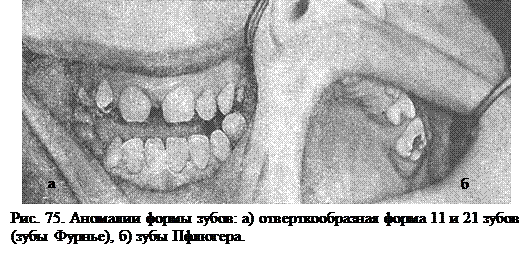

Фурнье указал, что для врожденного сифилиса характерна не полулунная вырезка режущего края центрального резца, а отверткообразная форма. Такой зуб носит название зуба Фурнье (рис. 75, а).

Зубы Пфлюгера – первые моляры, коронки которых напоминают нераспутвшийся бутон или почку (рис. 75, б).